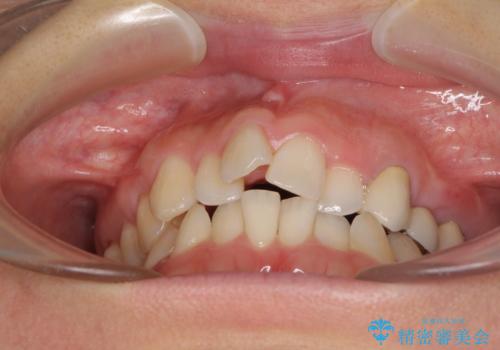

- 上下前歯のデコボコと銀歯のブリッジを気にして来院された患者様です。

装着されているブリッジを切断して矯正治療を行うことや、手間をかけずに早めに治療を終えたいとのことで、目立たないワイヤー装置による矯正治療を行うこととしました。